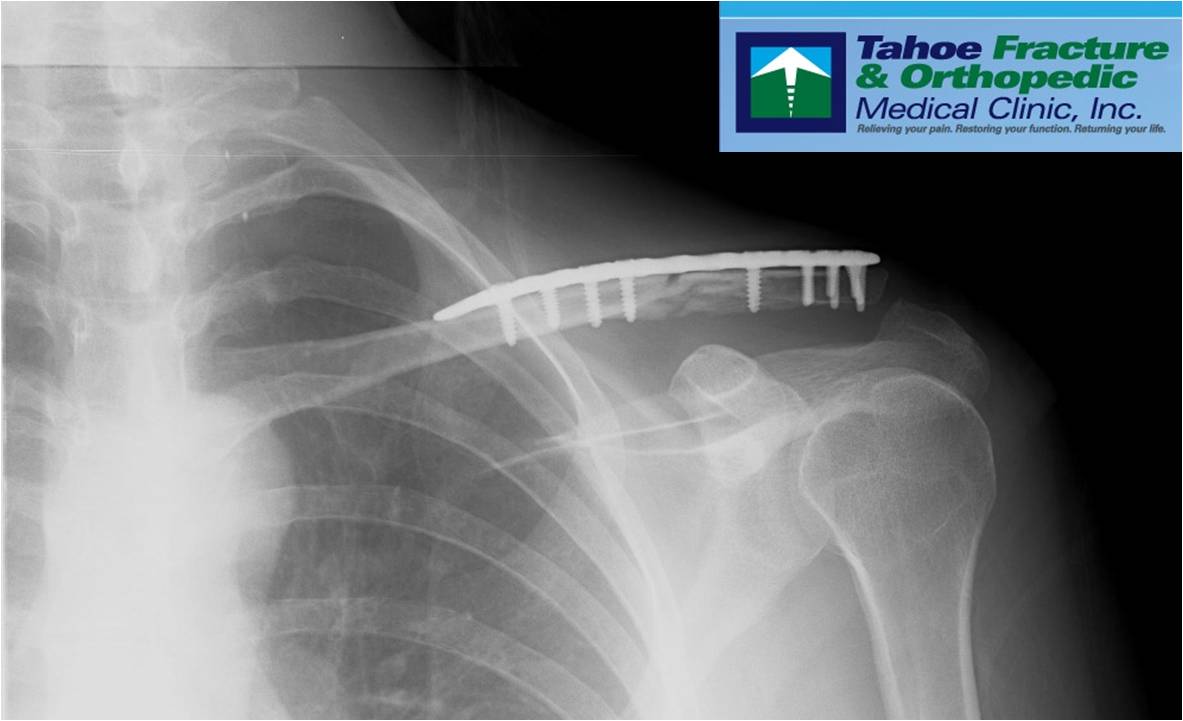

Nancy had an x-ray taken and Mike confirmed new bone growth was starting and things were looking good at the 5-week mark. Pete also took a look at the x-rays and agreed. Nancy and I were a little stunned to see EIGHT screws but we were told that this is all normal. The x-ray clearly shows new bone growth filling in the fracture gaps (light grey colour). An early April start for our ride when we return to Oz is still possible – review of final x-rays when we return will be key.